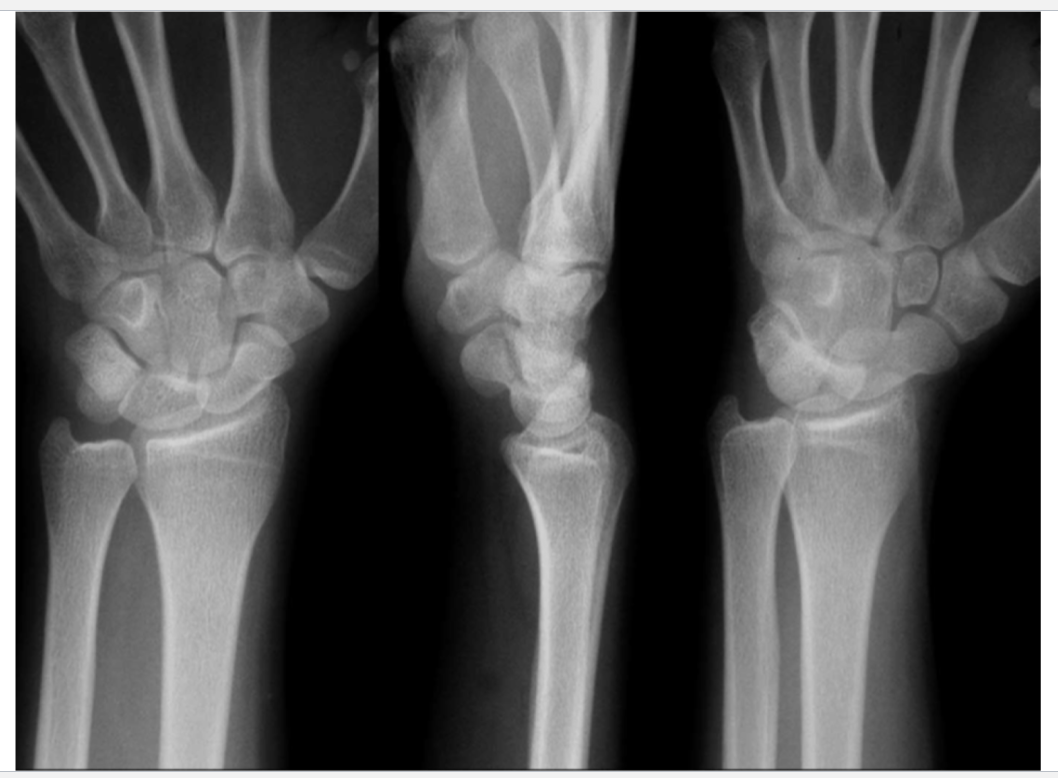

What is this?

Normal

Colles fracture